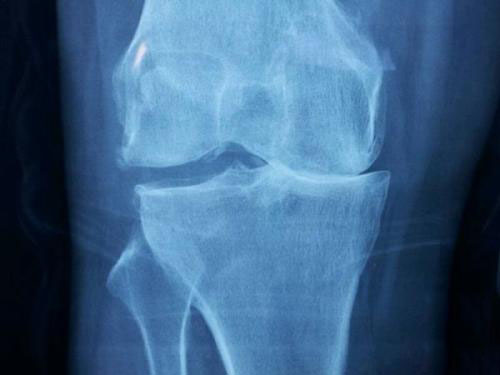

在正常的膝关节中,压力是平均分布在关节面上的,而O型腿的人,膝关节内侧的间隔狭窄变形,膝关节承受的压力会偏向内侧,导致内侧关节面在活动时受到的摩擦力更大,关节软骨更容易磨损,因此更容易患上膝骨关节炎。